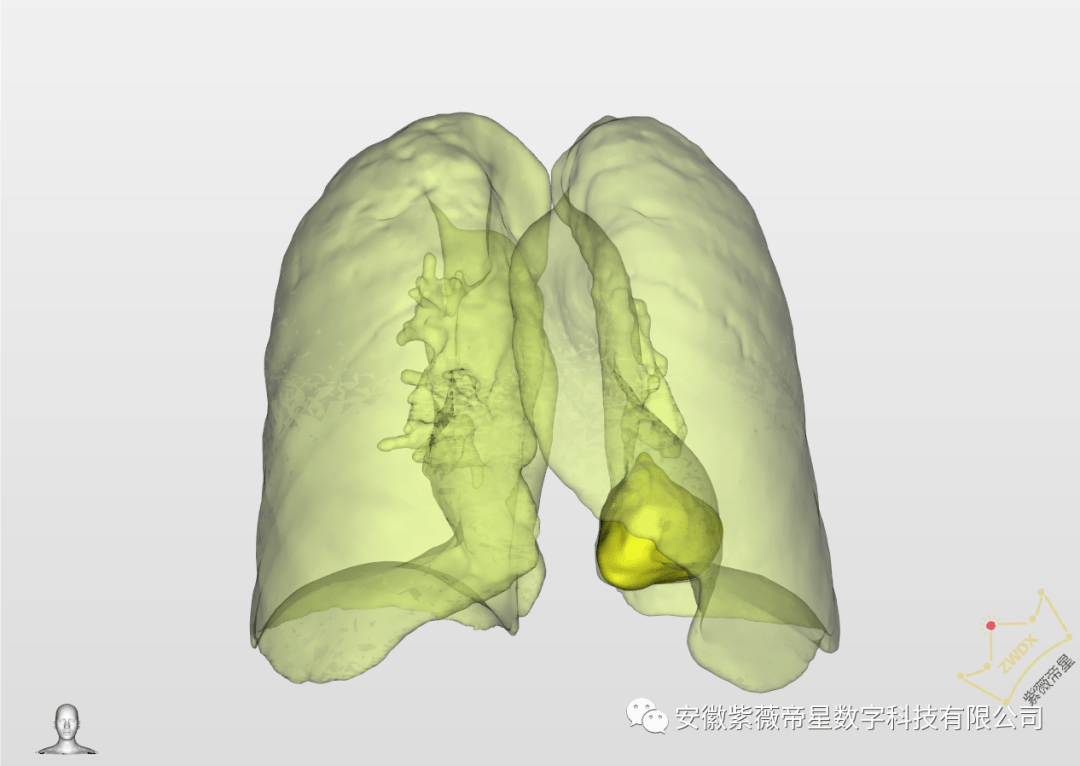

肺部ct三维重建,ct三维重建

new0466:肺部ct三维重建

肺部ctp1

肺部ct

正常肺部ct图

肺部ct图片